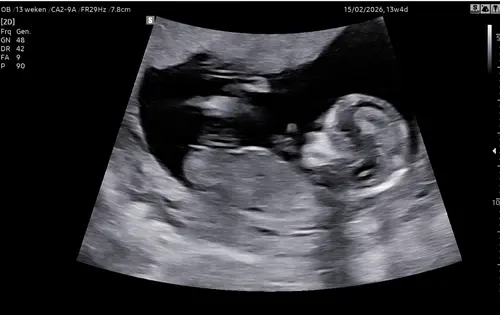

Vandaag precies 13 weken en de echo gehad! Al willen wij het tot het einde niet weten wat het wordt, ben ik toch benieuwd wat jullie denken te zien! ☺️ Gewoon voor later om te zien of het klopte 😉

Hier 13+2, iemand een idee? 🩵🩷

Iemand idee 13+5 🥰